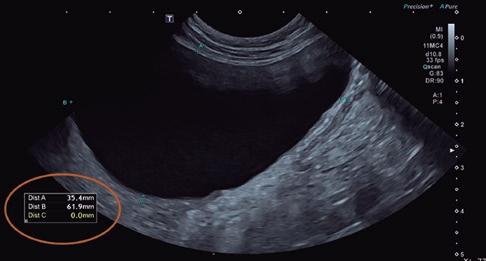

Estudio ecocardiográfico

• Modo B: en la proyección paraesternal derecha eje largo, se observó un jet de regurgitación mitral con dirección posterior y SAM (figura 3). En el eje corto derecho a la altura de la base cardiaca se observó un ratio atrio izquierdo/aorta (AI/Ao) de 1,92 (>1,6 se considera dilatación AI) (figura 4). Además, se observó hipertrofia de la pared del septo interventricular (SIV) de 7,6 mm y la pared libre del ventrículo izquierdo (PLVI) la 8,4 mm (hipertrofia >6 mm) (figura 5).

• Modo M: en paraesternal derecho eje corto a nivel de músculos papilares se observó un aumento del grosor del SIV en sístole (SIVs) de 7,8 mm (hipertrofia >6 mm), así como una hipertrofia de los músculos papilares (figura 6). • Modo Doppler: en la proyección paraesternal izquierda apical cuatro cámaras se midieron los flujos mitral (onda E 0,89 m/s y onda A 0,66 m/s) y subaórtico (4,56 m/s) (figura 7) ambos turbulentos, pero con velocidades dentro de rango. Presencia de ODTSVI. El flujo dentro de la aurícula izquierda estaba ligeramente disminuido (0,23 m/s, rango <0.25 m/s), aunque sin smoke